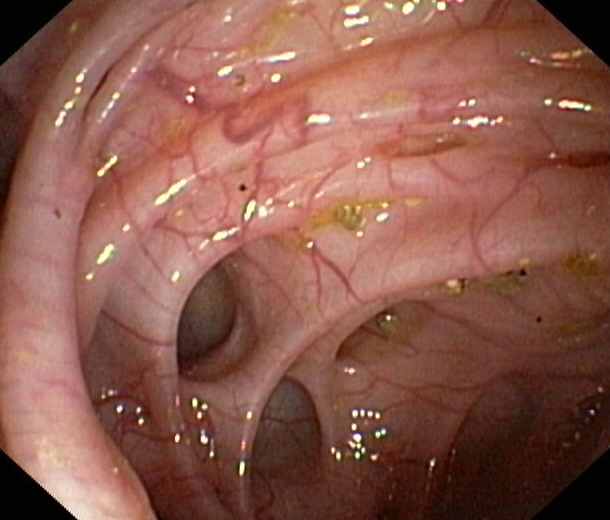

Duodenum:

Tubulovillous adenoma in the descending part of the duodenum